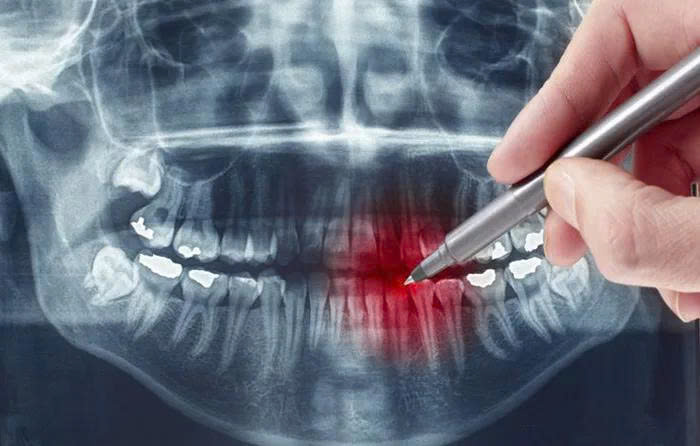

Bước 1: Khám và chẩn đoán

Bác sĩ thăm khám tổng quát, đánh giá mức độ sâu răng. Trường hợp cần thiết sẽ chỉ định chụp phim X-quang để xác định chính xác vùng tổn thương.